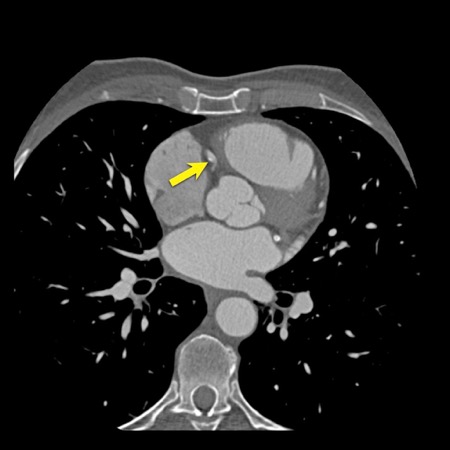

case 1 – CAD-RADS 2/P1

First, scroll through the scan.

Not all images are included. Some images without any abnormalities are skipped

from the series.

How would you describe the findings on the coronary CTA?

The findings are:

- Agatston score of

this patient was 14 (P1). Please, also note the calcification of the aortic valve. - Some partially

calcified and calcified plaques are present in the LAD with mild stenosis

(25-49%). - Calcified-plaque in

the LCX causing minimal stenosis (<25%). - Non-calcified

plaque in the distal RCA causing minimal stenosis (<25%). - This patient classifies

as CAD-RADS 2/P1, which means no further workup is needed.